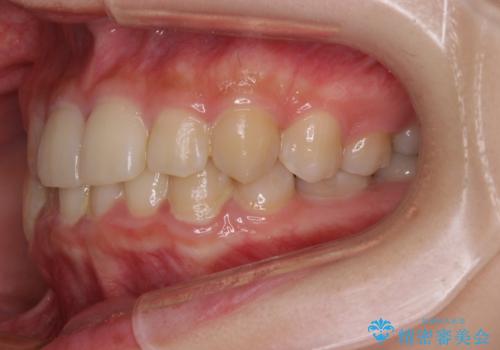

- クリアブラケット

- 犬歯のクロスバイトを気にして来院された患者様です。

マウスピース矯正とワイヤー矯正の両方を提案しましたが、インビザラインの自己管理が煩わしいとのことで、ワイヤー装置による矯正治療を行うこととしました。

犬歯は歯根が太くて長いため、クロスバイトを改善するのは大変であることが多いですが、比較的スムーズに改善することができました。

インビザラインであったら、もっと期間はかかっていたような印象です。